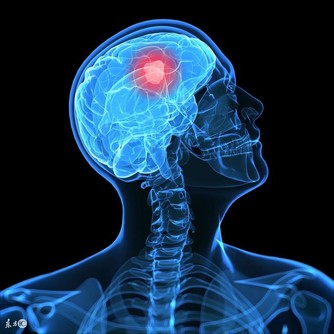

4. 腦子越來越不好使

那些睡得太晚太少的人,“起床氣”往往很嚴重,因為他們感到沮喪。而且如果你晚睡是在進行腦力勞動,更容易讓大腦負擔過重,由於無法得到正常休息,於是大腦的記憶、分析、學習能力都會下降,你也會發現自己反應越來越遲鈍。